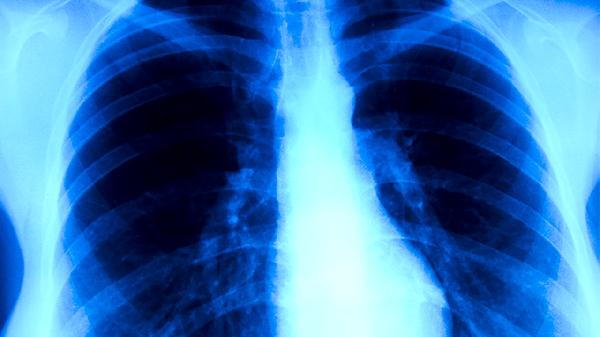

支原體肺炎低燒通常持續(xù)7-14天恢復(fù)正常,實際恢復(fù)時間與年齡、免疫狀態(tài)、治療時機、合并癥及護(hù)理措施等因素相關(guān)。

恢復(fù)期建議選擇高蛋白、高維生素飲食,如魚肉、雞蛋、新鮮果蔬等,避免辛辣刺激食物。每日進(jìn)行呼吸訓(xùn)練如腹式呼吸,每次10分鐘,有助于改善肺功能。體溫正常后仍需觀察1周,若出現(xiàn)反復(fù)低燒或咳嗽加重,需及時復(fù)查胸片。保持充足睡眠和適度活動,避免劇烈運動誘發(fā)心肌損傷。